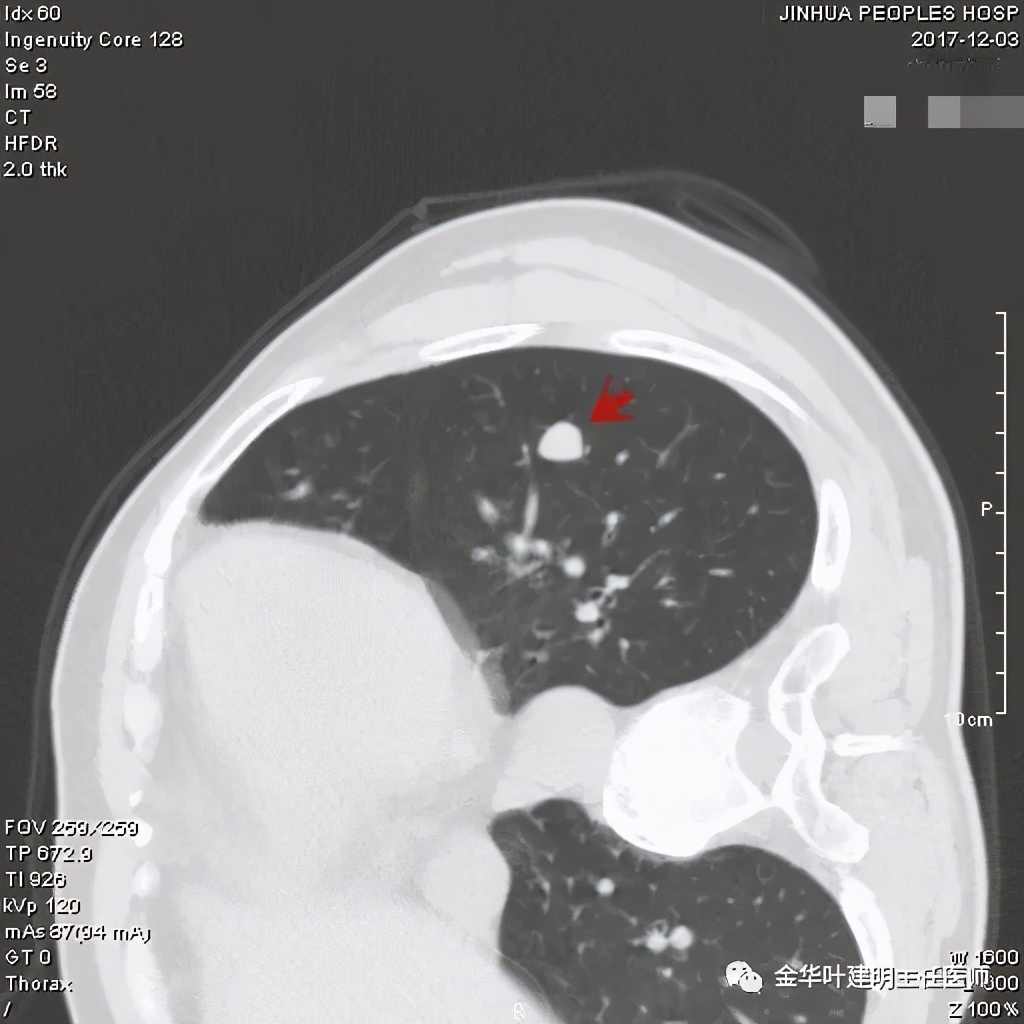

上图示病灶边缘过于光滑(绿色);局部有点状钙化(蓝色)

上图示病灶边缘过于光滑(绿色);血管贴边(桔色);

上图示病灶边缘过于光滑(绿色);血管贴边走行(桔色)

以上几图也示病灶边缘过光(绿色);血管贴边,感觉没受侵犯(桔色)

肿瘤不能除外,手术是正确及时的,回头看不知道有没有局部楔形切除或剜出肿瘤的可能性?下面是标本的病理:

其实今天分享这个病例与我们以往的错构瘤不太一样,以前的影像如下:

密度略不均,但边界甚清,边光峭

周围,边缘非常清,病灶内部有点状高密度,约1厘米许,似有微血管征